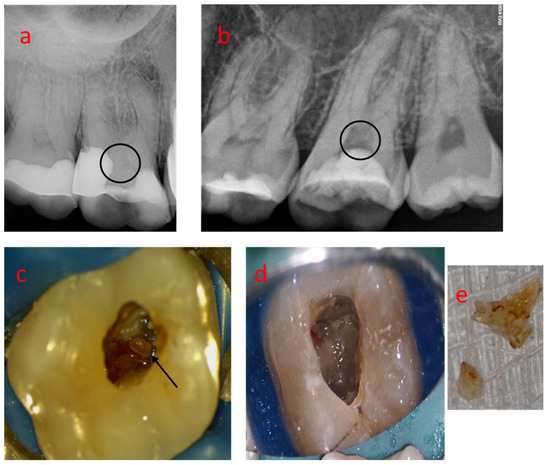

3.2. Sample 02

3.3. Sample 03